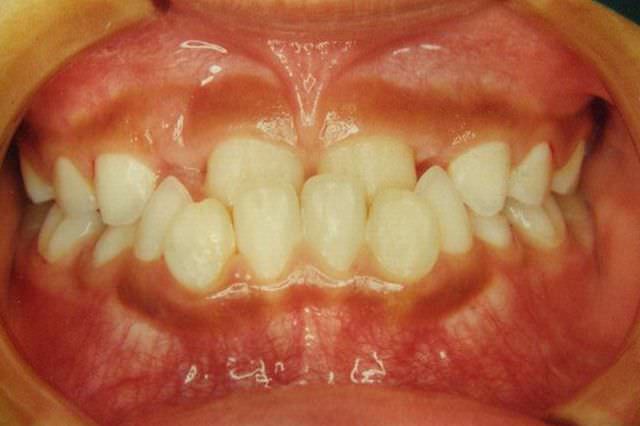

治療前

叢生 治療前

治療後

叢生 治療後

主訴 歯並びが気になる

診断名あるいは主な症状 叢生 乱ぐい歯

年齢 13歳0ヶ月

治療に用いた主な装置 ブラケット装置 スタンダードエッジワイズ法

抜歯部位 非抜歯

治療期間 2年5ヶ月

治療費概算 70万+月々の調整料

リスク副作用 歯の根が吸収して短くなる場合があります。

歯茎が痩せて下がる場合があります。

舌で歯を押す唇を噛む等の癖が改善されない場合は、治療期間が長引く場合があります。

定期的に通院できない、キャンセルが多い場合は治療期間が長引きます。